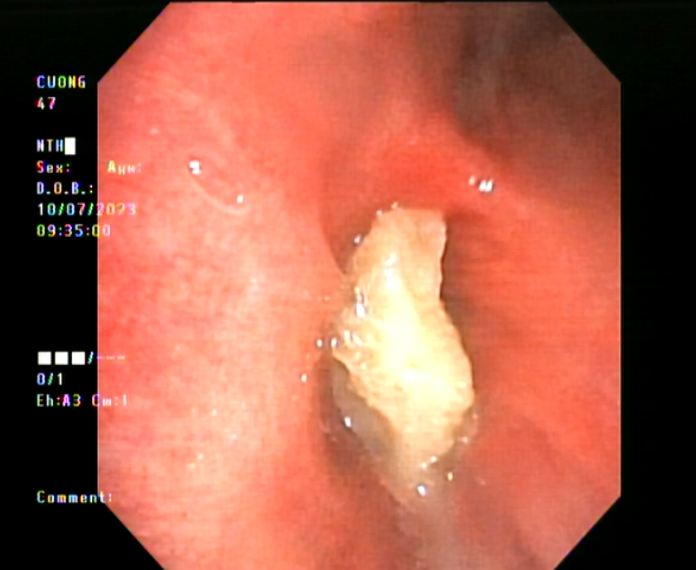

Cũng trong tuần này, ngày 10/7/2023, tại Bệnh viện Phổi Bắc Giang cũng vừa xử lý thành công gắp dị vật là một mảnh xương cho một bệnh nhân nam, 47 tuổi.

Hình 3: Hình ảnh dị vật ở bệnh nhân nam 47 tuổi